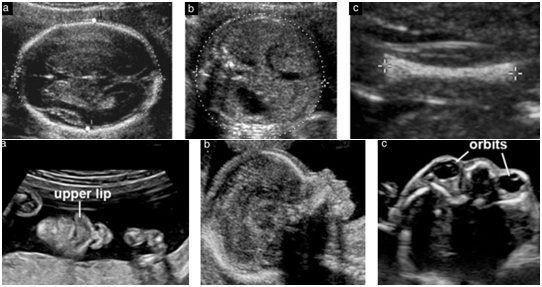

அனோமலிஸ்கேன் செய்யும்போது, மண்டைஓட்டின் உட்பகுதி, மூளை அமைப்பு, முகம், லென்ஸ்கள், மூக்கு, உதடுகள், கன்னம், இதய அமைப்பு, நுரையீரல், வயிறு, இரண்டு சிறுநீரகங்கள், குடல்கள், சிறுநீர்ப்பைகள், மூட்டுகளின் பகுதிகள் கொண்ட இரண்டு கண் சுற்றுப்பாதைகள் ஆகியவற்றிற்கு சிறப்பு கவனம் செலுத்தப்படுகிறது. கைகள் மற்றும் கால்விரல்கள்.

குழந்தையின்காதுகள், விரல்கள் மற்றும் கால்விரல்களின் எண்ணிக்கை ஆகியவை குறிப்பிடப்பட்ட மற்றபாகங்களில் ஏதேனும் அசாதாரணங்கள் இருந்தால் மட்டுமே பரிசோதிக்கப்படும். கூடுதலாக, உங்கள் குடும்பத்தில் மரபணுகோளாறு இருந்தால் இதுவும் பரிசோதிக்கப்படுகிறது.